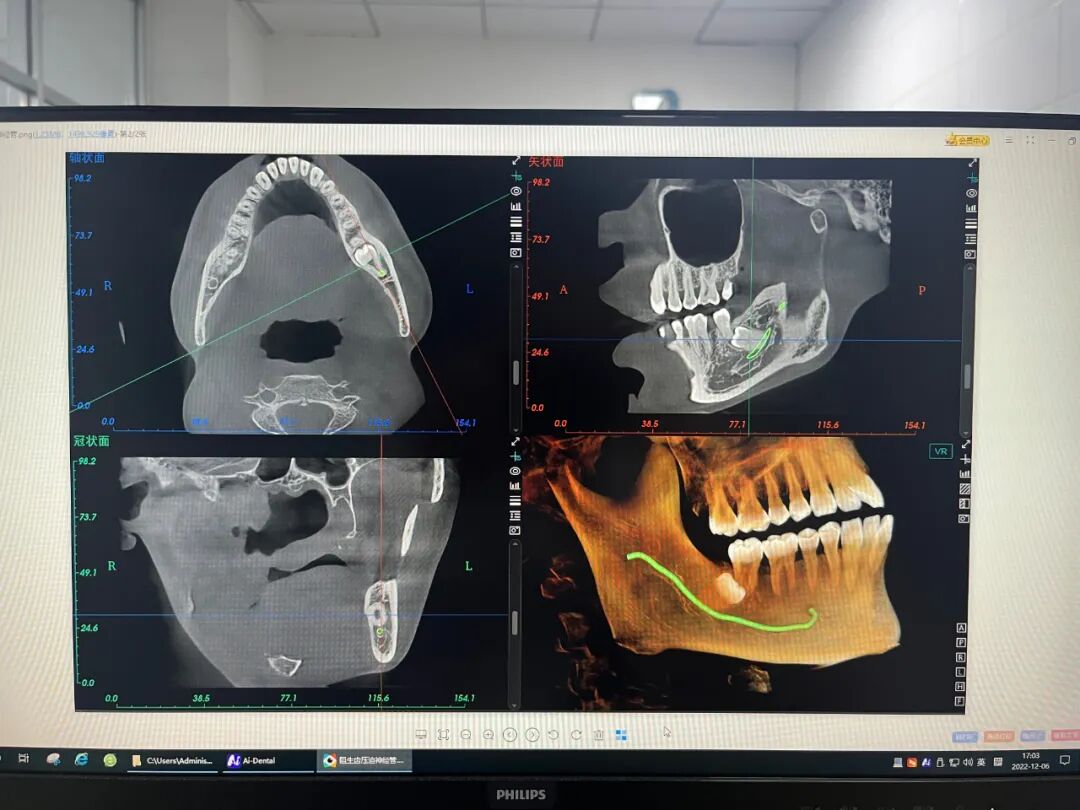

口腔ct怎么拍摄【医院动态】口腔科的“火眼金睛”——CBCT投入使用_https://www.jmylbn.com_新闻资讯_第5张(绿色线条为下颌神经管)

2. 口腔CT(锥形束CT):可从三维角度对组织情况进行反映,准确清晰地诊查各组织的健康状态,病损范围及与周围组织间的关系以及发现更加细微的病变,诊查各类阻生牙的位置状态及与临近的神经和窦腔的位置距离,协助医师们在进行术前方案设计以及术后科学评价,还可清晰地检查牙槽骨内的病损。

口腔ct怎么拍摄【医院动态】口腔科的“火眼金睛”——CBCT投入使用_https://www.jmylbn.com_新闻资讯_第6张